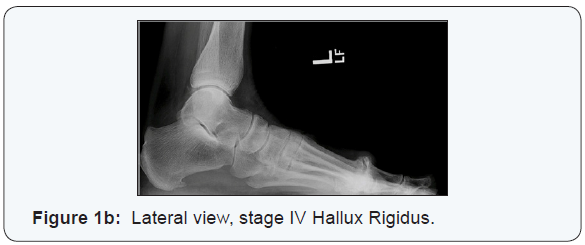

Motion loss of 50% to 75% is present. In Grade III, pain is usually constantly exacerbated by plantar flexion and dorsiflexion of the hallux. Subchondral cysts and sesamoid bone involvement are radiographically evident, with 75% to 100% loss of motion. In Grade IV, similar findings of Grade III are seen, but patient’s present with pain throughout the mid-range of motion on clinical examination [3] (Figures 1a & 1b). Patients presenting with Hallux limitus/rigidus may initially be managed with non-operative treatment. Stiff-soled shoes, non-steroidal anti-inflammatory drugs, corticosteroid injections and orthotics are commonly employed. Surgical options include but are not limited to cheilectomy, osteotomy, arthroplasty and arthrodesis. This study looked at first metatarsal phalangeal joint fusions with cannulated crossing screws and a dorsal, low profile neutralization plate (Flower Orthopedics, Horsham PA) in association in association with early weight bearing.